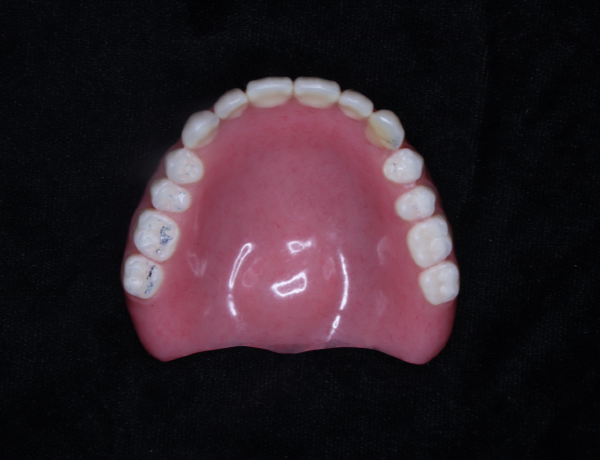

上あご

患者さんのかみ合わせやかむ力を考慮して、金属の入れ歯を選択しました。写真を見ると分かると思いますが、入れ歯の金属の部分がとにかく大きく広くとってあります。この金属の設計は、先代の田中久敏に習ったデザインになりますが、口蓋の吸収しない部分は、金属で出来るだけ広く覆って、それ以外の部分は、ピンクのレジンで覆っています。

このように金属の部分を大きくすると強度が増しますので、割れたりヒビが入ったりする可能性が少なくなります。